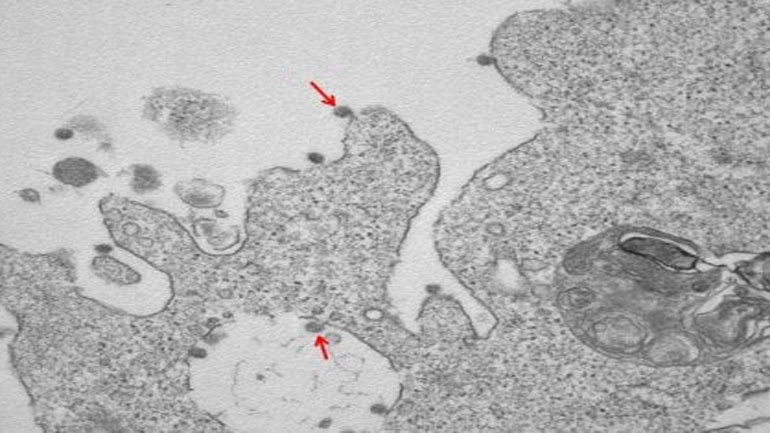

Το εργαστήριο των μολυσματικών ασθενειών του νοσοκομείου Sacco στο Μιλάνο έδωσε τις πρώτες εικόνες στις οποίες φαίνεται ο κορωνοϊός μέσα από ηλεκτρονικό μικροσκόπιο. Ο ιός απομονώθηκε από συγκεκριμένη ιατρική ομάδα υπό τους καθηγητές Massimo Galli και Gianguglielmo Zehender σε συνεργασία με το Τμήμα Παθολογικής Ανατομίας, αλλά και την καθηγήτρια Manuela Nebuloni του Τμήματος Βιοϊατρικών και Κλινικών Επιστημών Luigi Sacco. Η ανακοίνωση έγινε από το κρατικό πανεπιστήμιο του Μιλάνου.

Στη φωτογραφία, σε μεγέθυνση παρατηρούνται τα ιικά σωματίδια του SARS-CoV-2 (υποδεικνύονται με βέλη), τα οποία συνδέονται με τις μεμβράνες στην επιφάνεια και εντός των κυττάρων VERO E6, που χρησιμοποιούνται για απομόνωση.